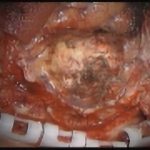

摘出 中

摘出 後